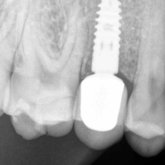

He received his Diploma in Implantology in 2016 from the University of Pretoria, which he passed with Distinction. He is also a member of the International Team for Implantology (ITI), which is based in Switzerland and offers members access to the latest research and cutting-edge techniques.